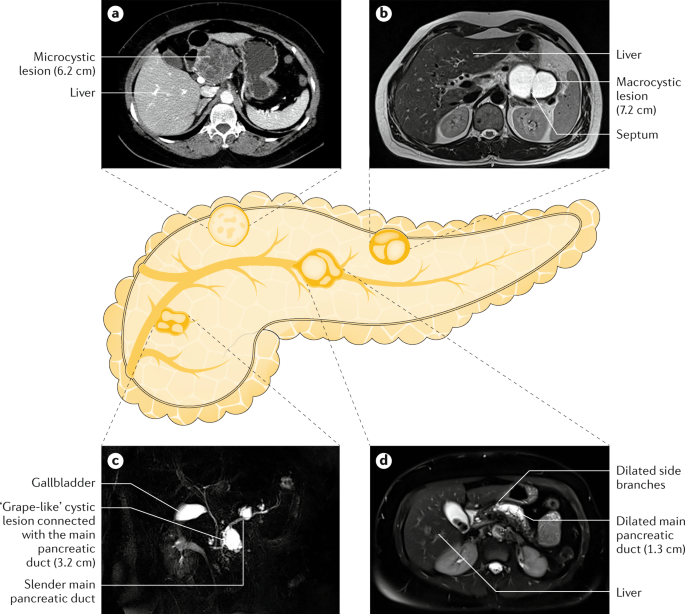

For many patients, a pancreatic cyst — which may not be a true cyst but a pseudocyst that lacks the specialized cells that secrete fluid into the space they occupy — will go away without treatment Many doctors prefer to use a method called watchful waiting, where no treatment is given and the cyst is monitored for changes Often, a benign cyst will resolve within six weeks and no Serous cystadenomas are benign focal cystic lesions which usually include multiple, small (12 cm in diameter) cysts separated by thick fibrous septa, resembling a honeycomb (Fig 4) They can be located anywhere in the pancreas and are rarely malignant, opposite to IPMNs and mucinous cysts Lymphoepithelial cysts are very rare cystic lesions of the pancreas They usually measure less than 5 cm and are seen in men The cysts are lined by squamous epithelium and surrounded by dense lymphoid tissue Their imaging appearances vary and they may be either unilocular or multilocular

Due to the widespread use of imaging, small 1–3 cm cystic masses in the pancreas are being more commonly seen in asymptomatic individuals As true epithelial cysts of the pancreas are extremely rare, these are a diagnostic problem Some believe that they may represent side duct intraductal neoplasms, and recommend followup to ensure stability An ERCP or MRCP6 1732 ACR guidelines Size Recommendation < 2 cmLEC of the pancreas is an uncommon type of pancreatic cyst first described by Luchtrath and Schriefers in 1985 6 Around 70 cases have been published so far 7 These lesions are usually benign and develop in middleaged patients (mean age, 55 y;

Diffuse parenchymal calcifications and pancreatic atrophy can also be seen in patients with advanced pancreatic insufficiency Associated with calcifications, small unilocular pancreatic cysts measuring 1–3 mm can also be seen; The cysts typically produce large amounts of mucus which sometimes can be seen draining out of the papilla of Vater at the time of endoscopic retrograde cholangiopancreatography (ERCP), a test that visualizes the ampulla of Vater and the pancreatic duct These cysts can cause abdominal pain, jaundice, and pancreatitis Increased risk for cancer occurs with older age of theThe traditional therapy is pancreatic resection and not cyst enucleation In contrast to cystic neoplasms, pseudocysts are localized collections of inflammatory fluid that mimic cystic neoplasms The fluid collections arise from chronic pancreatitis and ductal leaks Because pseudocysts have no neoplastic potential, they can be drained rather than resected Drainage can be safely